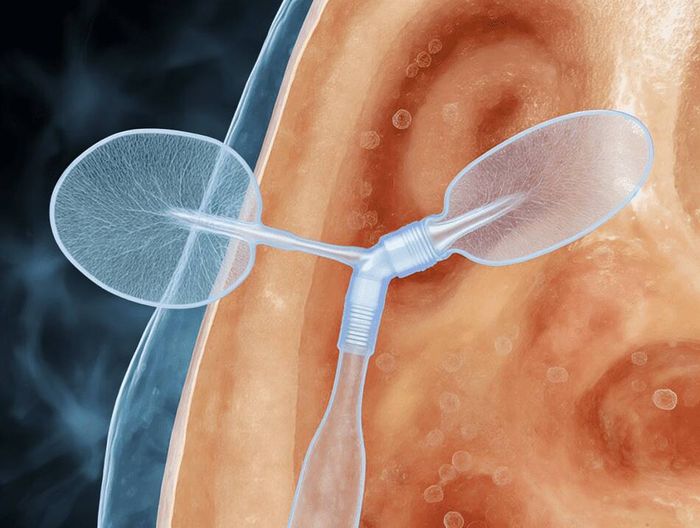

在医疗器械检测领域,生物相容性检测指通过细胞毒性、致敏、刺激等试验,评估材料与人体接触时的安全性,考察是否引发炎症、过敏等反应,是确保器械临床使用安全的关键检测。

其核心是依据相关标准,验证材料与人体组织的相容性,降低不良反应风险,为医疗器械的生物安全性评价提供科学依据。